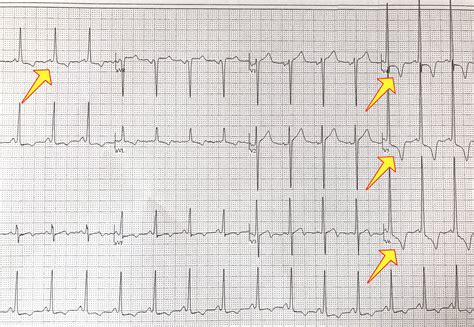

Some of the common ECG findings in HCM include:

• Left ventricular hypertrophy (LVH): This is characterized by increased voltage in the QRS complex, particularly in the precordial leads (V5 and V6).

• ST-segment and T-wave abnormalities: These can include ST-segment depression and T-wave inversions, which are often seen in the lateral leads (I, aVL, V5, and V6).

• Q waves: Deep Q waves in the lateral leads can also be indicative of HCM.

• Arrhythmias: HCM patients may experience various arrhythmias, including atrial fibrillation, ventricular tachycardia, and supraventricular tachycardia. These can be detected on an ECG.

Interpreting a Hypertrophic Cardiomyopathy ECG requires a thorough understanding of the normal ECG patterns and the specific abnormalities associated with HCM. Here are some key points to consider when interpreting an ECG in a patient suspected of having HCM:

• Voltage criteria for LVH: Look for increased voltage in the QRS complex, particularly in the precordial leads. Common criteria include the Sokolow-Lyon index (SV1 + RV5 or RV6 ≥ 35 mm) and the Cornell voltage criteria (RaVL + SV3 ≥ 28 mm in men and ≥ 20 mm in women).

• ST-segment and T-wave changes: Pay attention to ST-segment depression and T-wave inversions, especially in the lateral leads. These changes can be subtle and may require careful examination.

• Q waves: Deep Q waves in the lateral leads can be a sign of HCM, but they can also be seen in other conditions, such as myocardial infarction. Therefore, it is important to consider the clinical context and other diagnostic findings.

• Arrhythmias: Look for evidence of arrhythmias, such as atrial fibrillation, ventricular tachycardia, or supraventricular tachycardia. These can be detected on an ECG and may require further evaluation and management.